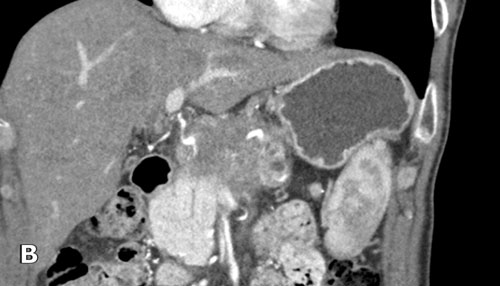

Hình CT axial cho thấy một động mạch gan phải phụ thêm (mũi tên vàng) đi qua vùng lân cận một khối giảm tỷ trọng ở đầu tụy (đầu mũi tên).

Sự liên quan mạch máu được đánh giá rõ hơn trên ảnh tái tạo mặt phẳng đứng dọc. Có sự áp sát 90 – 180° của động mạch gan phải thay thế (mũi tên trắng) bởi ung thư biểu mô tuyến đầu tụy (đầu mũi tên trắng).

Động mạch gan trái nguyên bản đi theo hướng ra trước hơn, tĩnh mạch cửa nằm ở giữa.

Cuộc phẫu thuật là cắt bỏ diện R1.

Các hình ảnh axial của cùng bệnh nhân có chú thích.